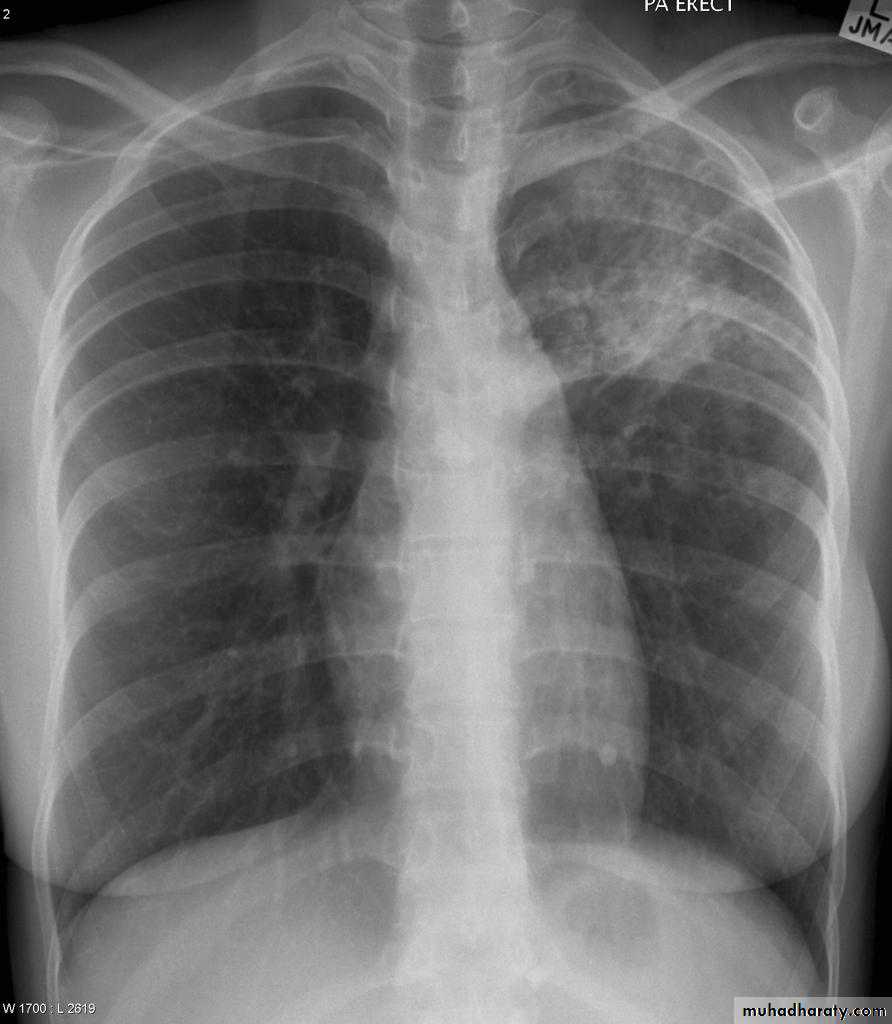

Pulmonary emphysema

Pulmonary emphysema is defined as the "abnormal permanent enlargement of the airspaces distal to the terminal bronchioles accompanied by destruction of the alveolar wall and without obvious fibrosis". Emphysema is one of the entities grouped together as chronic obstructive pulmonary diseaseRadiographic features

Plain film

Except in the case of very advanced disease with bulla formation, chest radiography does not image emphysema directly, but rather infers the diagnosis due to associated features :

hyperinflation:

1.flattened hemidiaphragm(s): most reliable sign

2.ncreased and usually irregular radiolucency of the lungs

3.increased retrosternal airspace

4.increased antero-posterior diameter of chest

5.widely spaced ribs

6.sternal bowing

7.tenting of the diaphragm

8.saber-sheath trachea

9.vascular changes paucity of blood vessels ( absent pulmonary markings in outer 1/3 of the lung fields )

10 .pulmonary arterial hypertension

pruning of peripheral vessels

increased calibre of central arteries

right ventricular enlargement

Emphyzema